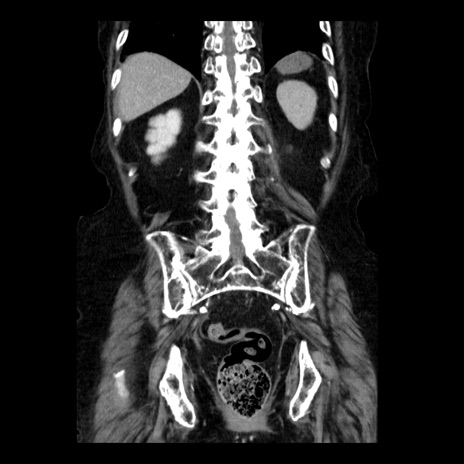

症例14(冠状断像)

【症例】 90歳代女性

【主訴】 腹痛・嘔吐

【現病歴】今朝から左側腹部痛を認めた。 経過観察していたが、嘔吐を認めたため来院。

【既往歴】 子宮癌術後

【身体所見】 意識清明、BP 127/54mmHg、P 98bpm Sp02 95%(RA)、BT 35.8°C、腹部平坦・軟腸ぜん動音聴取良好、右下腹部圧痛(+) 反跳痛なし

【データ】WBC 9800、CRP 0.46